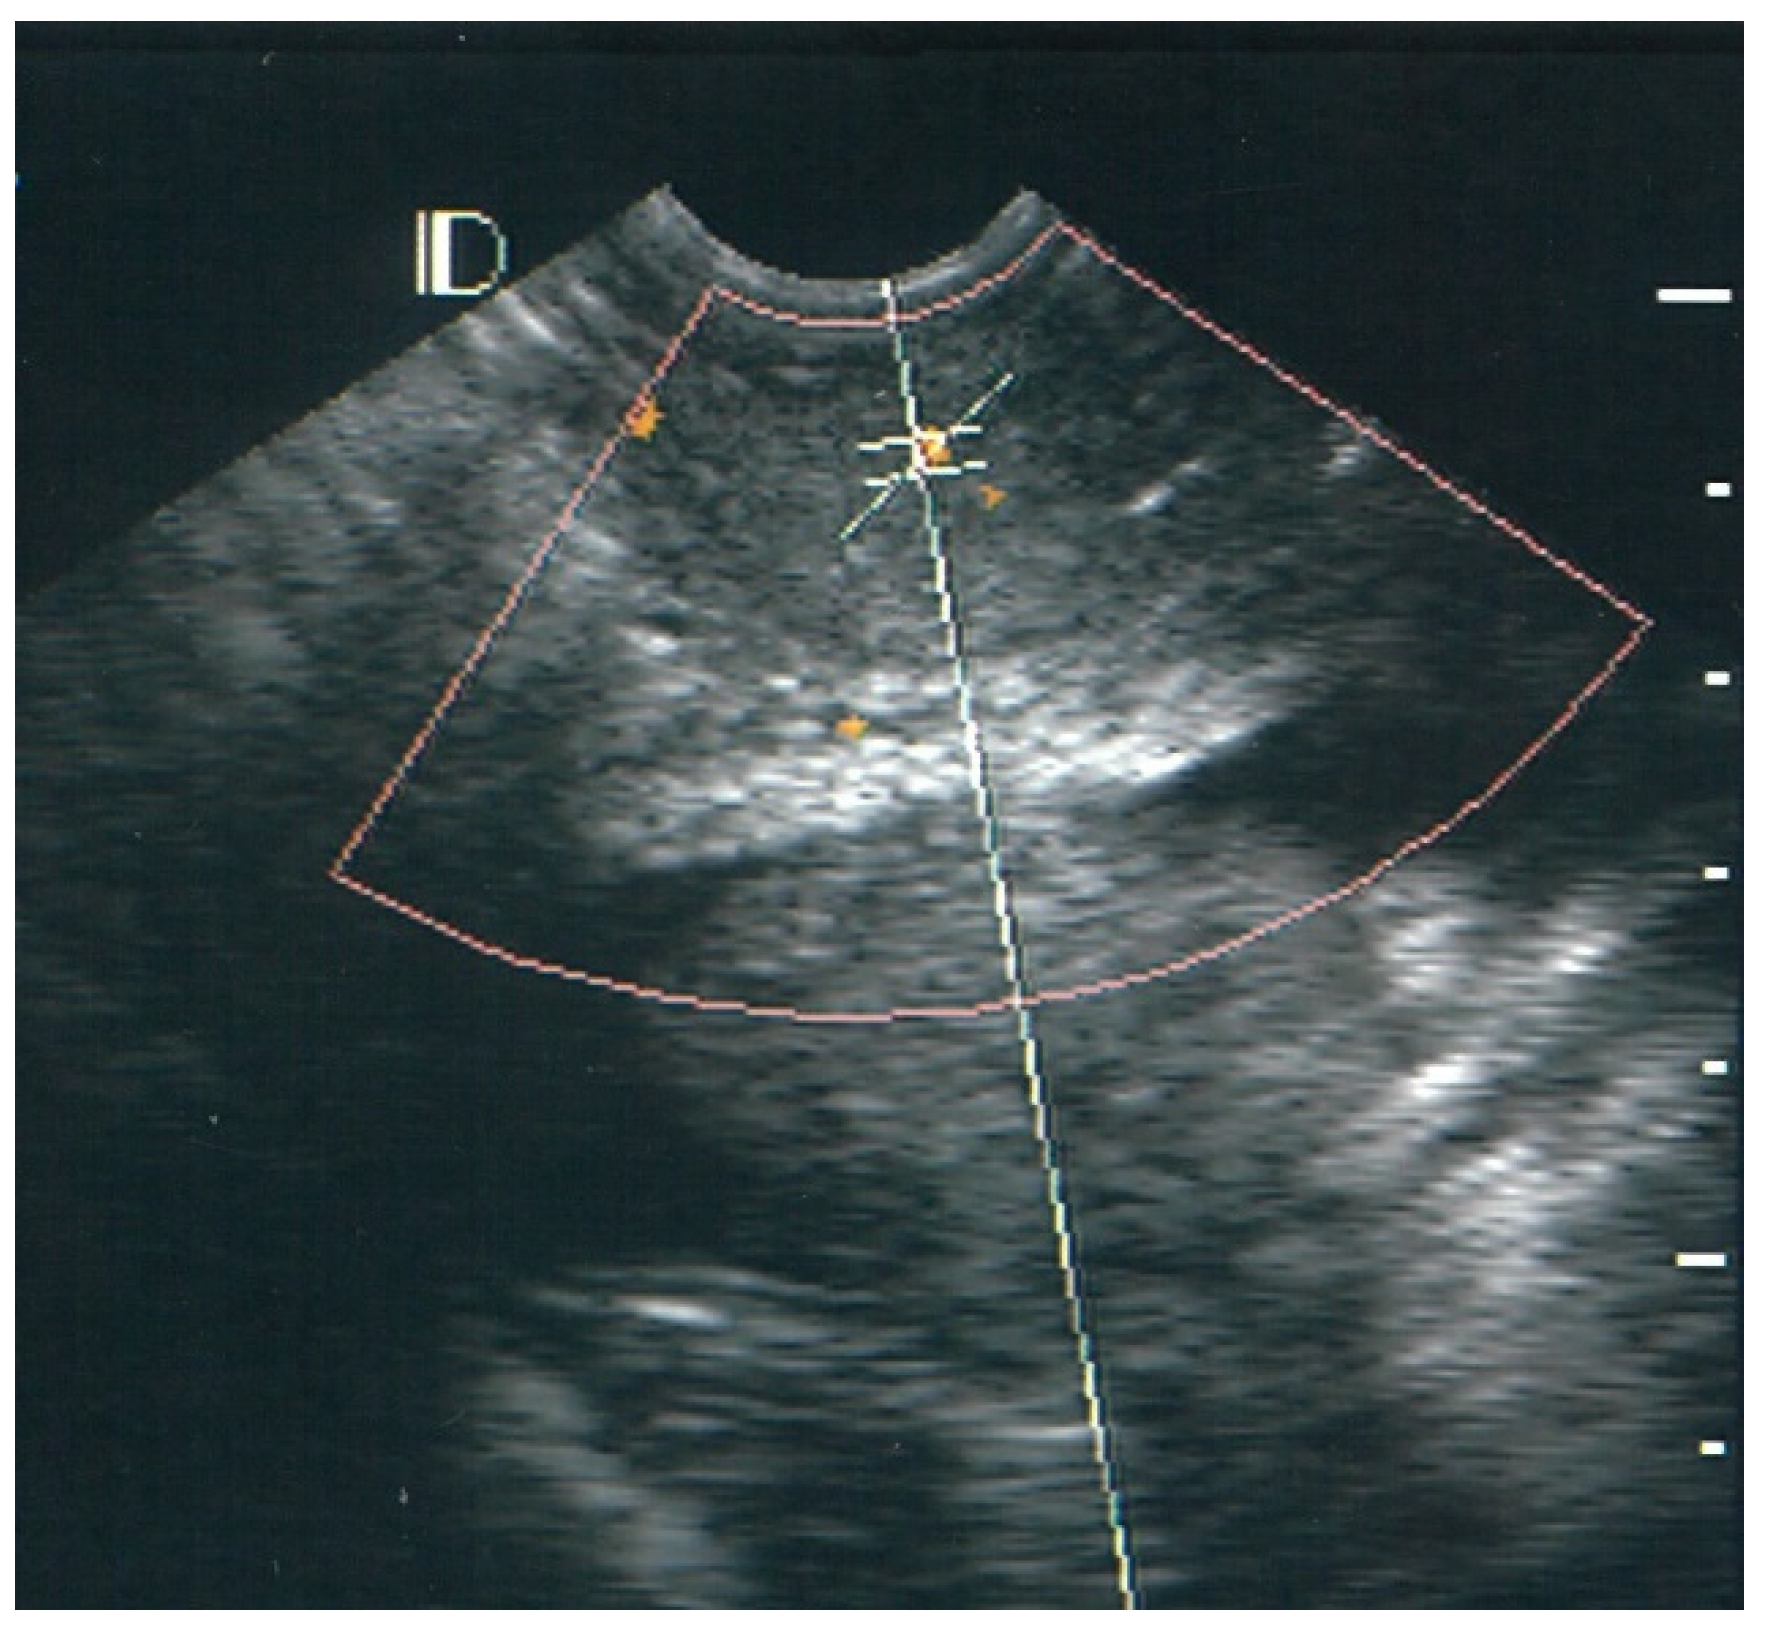

3.1. Visual Classification of Vascularity Findings on TV-PDU

| Classification | Numbers of Visualize Vascular Hotspots within Cervix (One Spot: 1 × 1 mm) |

|---|---|

| Class 0 | 0 |

| Class I | 1 to 5 |

| Class II | 5 to 10 |

| Class III | >10 |